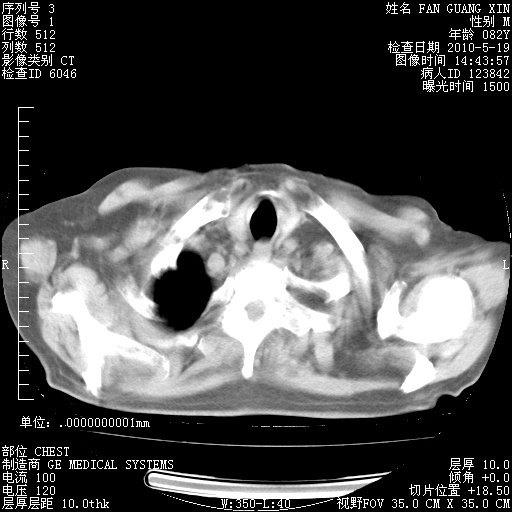

复查肺部CT,明显好转。为什么发热呢?

治疗3周后的肺部CT

治疗3周后的肺部CT纵隔窗